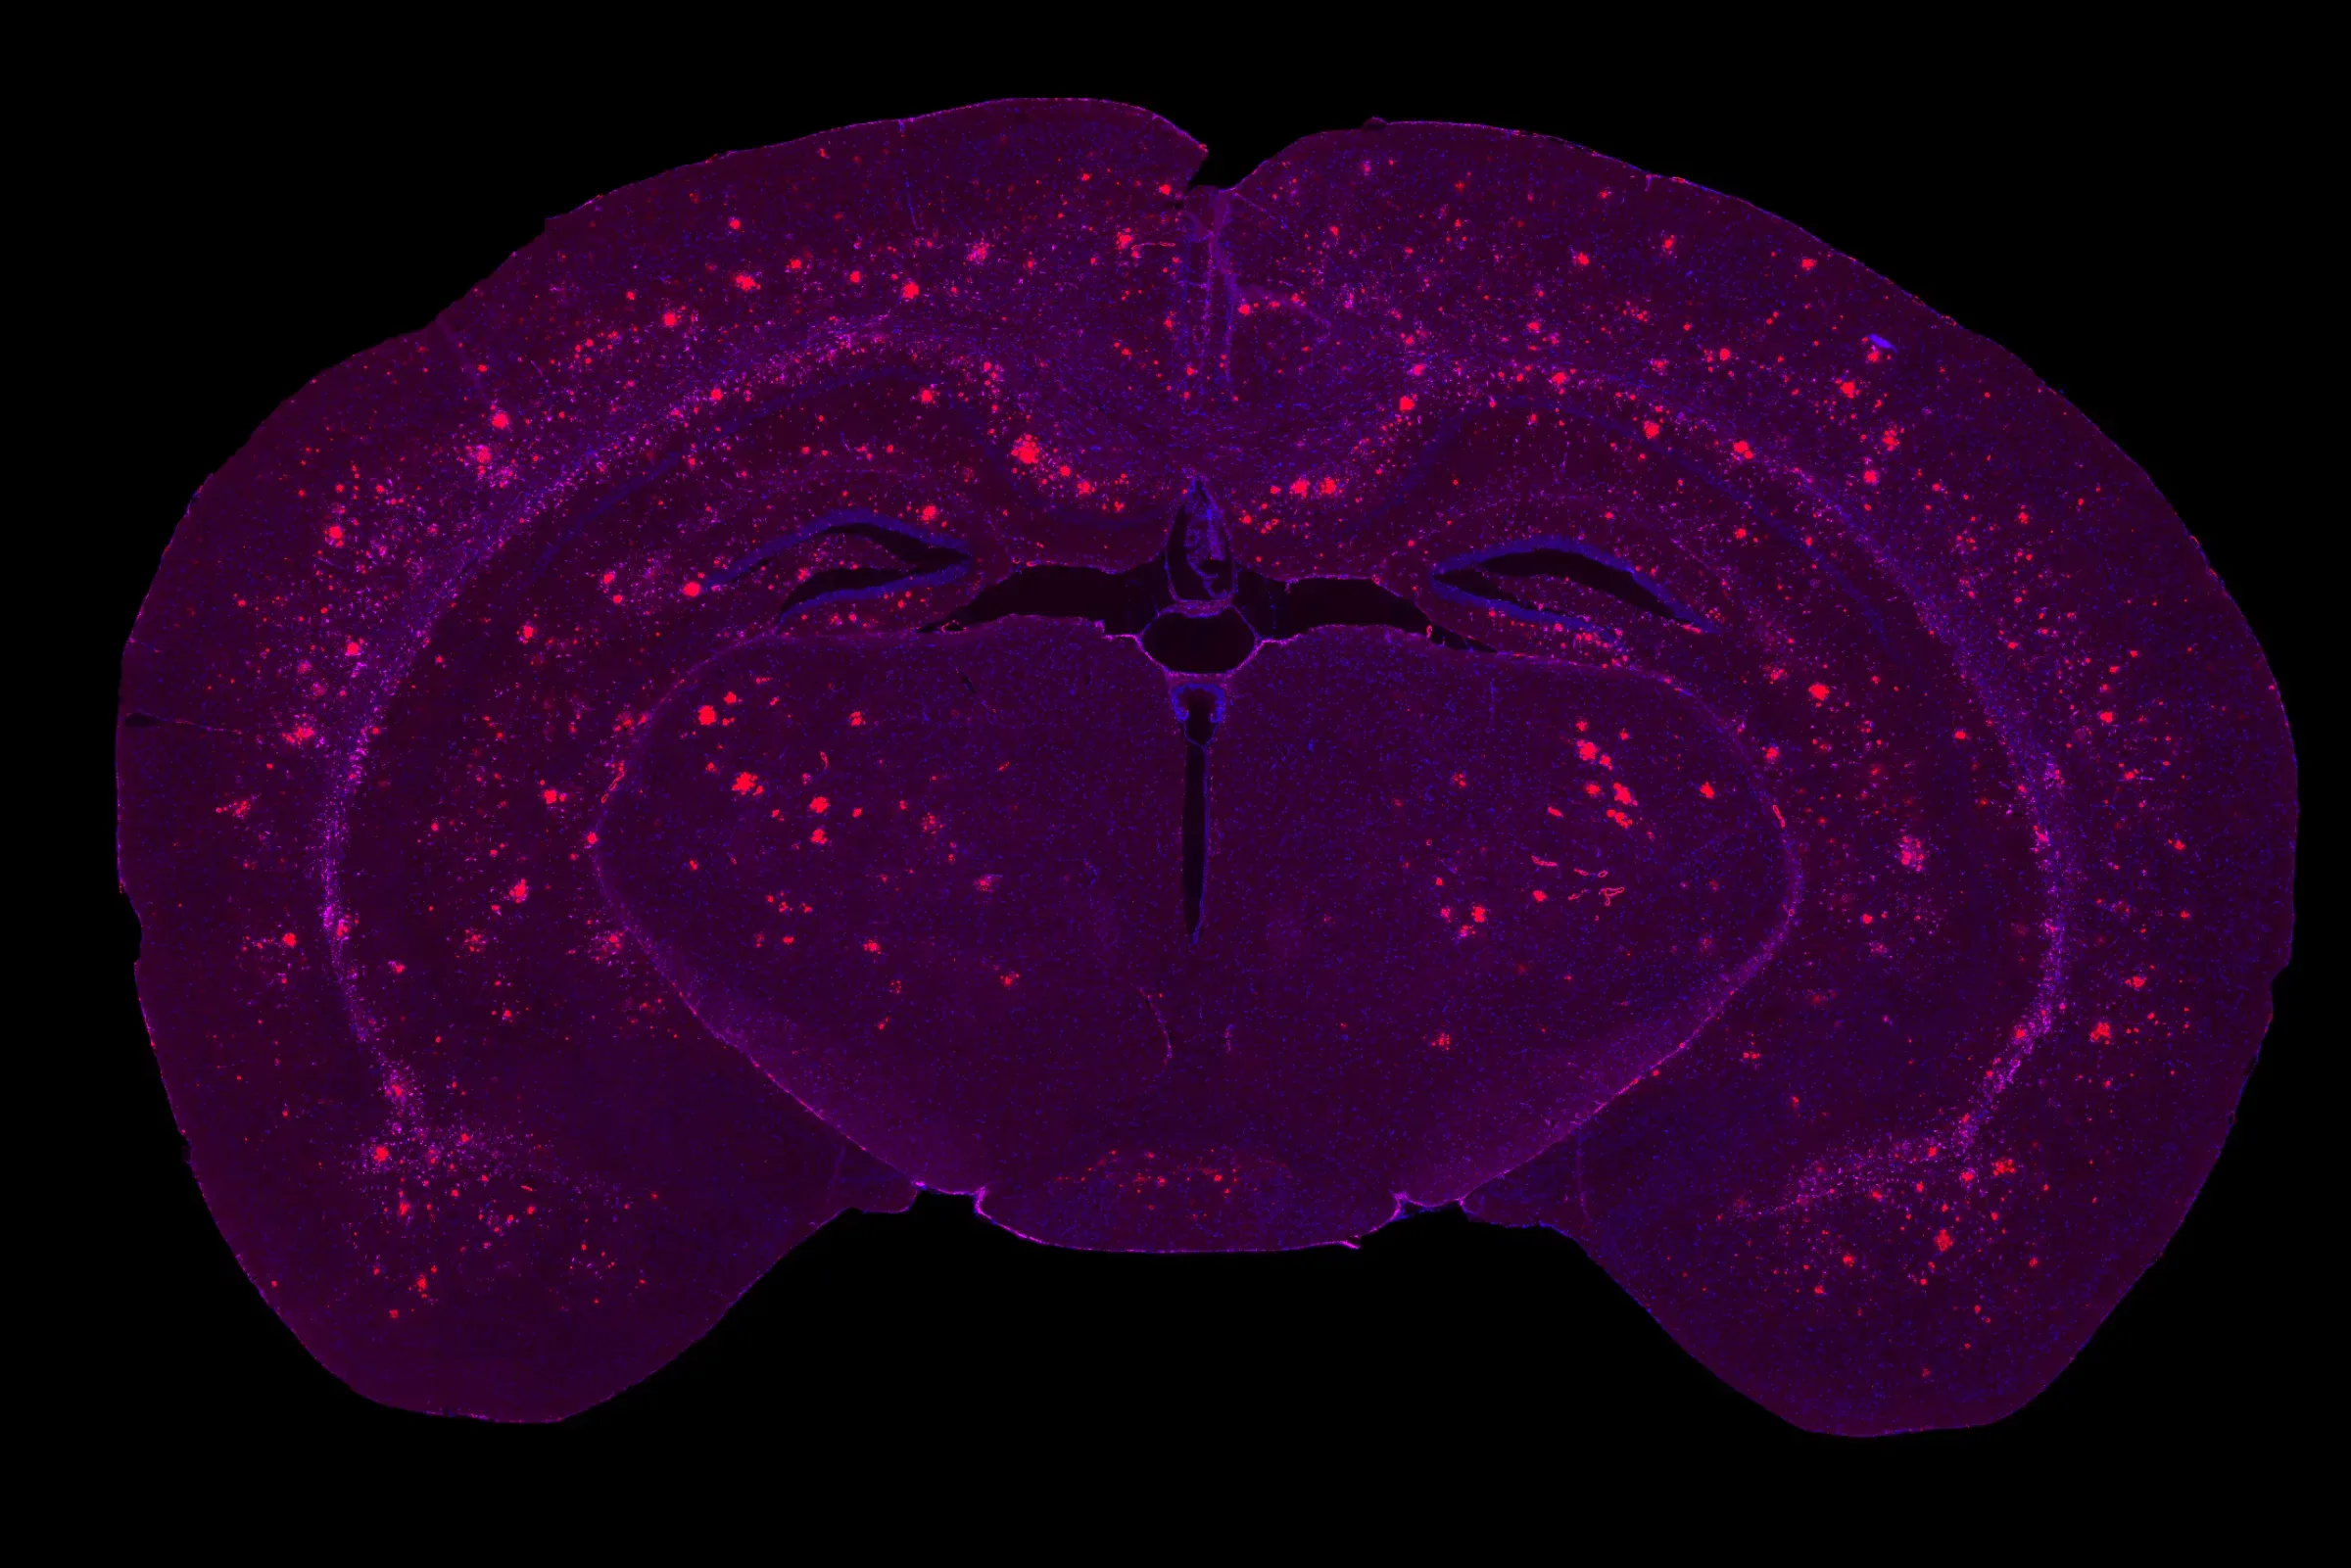

Multiplex IF of the brain of a 9 month-old APP/PS1 mouse showing a high Aβ pathology burden.

Time-dependent β-amyloid plaque formation in the frontal cortex of APP/PS1 mice.